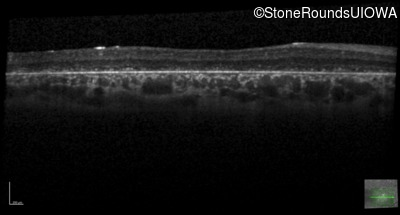

Age at visit: 6 years

OD OS

Age at visit: 5 years

Age at visit: 7 years

Age at visit: 8 years

Age at visit: 9 years

Age at visit: 11 years

Age at visit: 12 years

Age at visit: 13 years

Age at visit: 14 years

Age at visit: 17 years